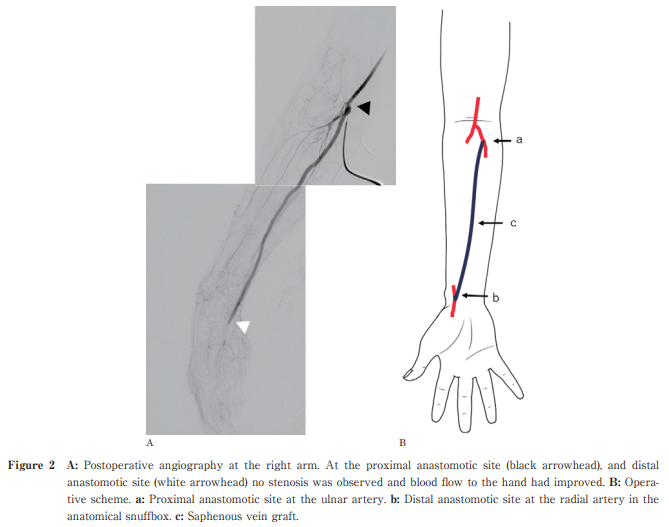

Novel Approach to Upper Extremity Ischemia: Radial Artery Bypass Surgery in the Anatomical Snuff Box for Upper Extremity Critical Ischemia Leading To Hand Gangrene : A Case Report

https://doi.org/10.51040/dkmj.2023-065

Masahiro Tezuka et al.

Published online : December 26 , 2024